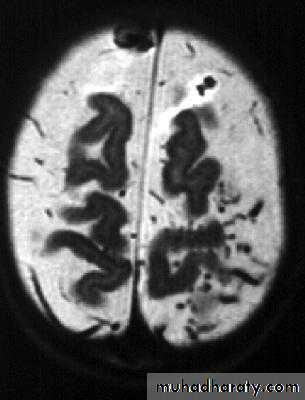

• B. Radiological Investigations:• CT or MRI is the investigation of choice.

• CT Brain is performed with and without contrast.

• MRI is done with gadolinium enhancement.

• They will show a single (or multiple) space occupying lesion that is well delineated with an enhancing wall, with variable surrounding oedema.

Brain Abscess CT without contrast

Brain Abscess CT with contrast

Brain Abscess MRI